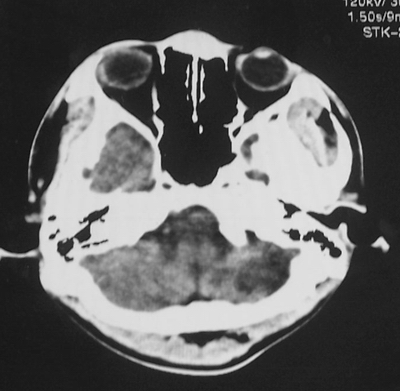

患者、男、18y,头痛5天入院。

左小脑、右丘脑区低密度影,无明显强化及占位表现,男18y,先考虑脑部炎性病变,如脑炎、血行播散性感染等,建议结合临床如脑脊液检验。

单独看左侧小脑半球的不规则形囊性低密度灶,从发病部位、年龄以及无强化、无占位效应的特点可以考虑毛细胞瘤型星形细胞瘤。同样,如果单独看右侧丘脑的近圆形低密度,也可以考虑囊变形星形细胞瘤。只是胶质细胞瘤一般为单发直接浸润、蔓延生长,而不是在脑内同时出现多个病灶,且瘤周没有一点儿水肿,暂时不予以考虑。

同时,现在已经进入冬天,一氧化碳中毒也需要考虑进去。不知道增强是什么时间做的,与平扫间隔几天?如果中间时间比较久而且进行吸氧等治疗,则平扫所示右侧颞叶密度比较低、右侧小脑半球以及脑桥也似有片囊状低密度,但在增强却没有发现就可以比较合理的解释了。